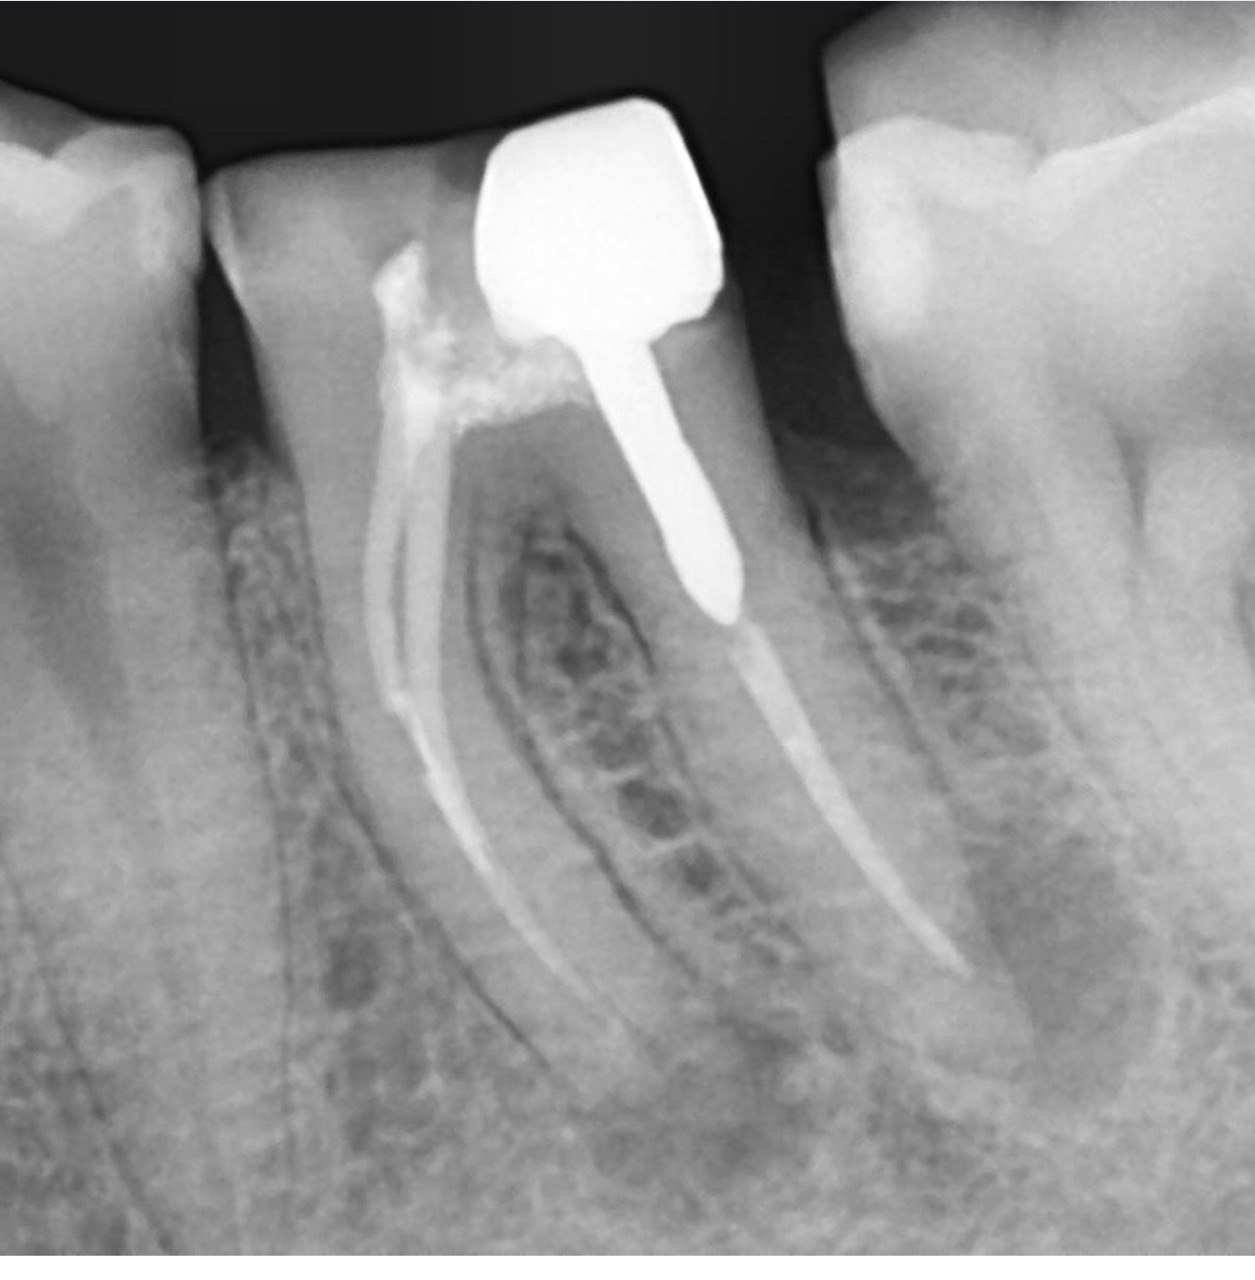

Question 21: What option is can be selected for distal tooth # 4.6?

Question 22: Which surface shows defective restoration?

Question 23: Which surface shows overhang?

Question 24: Which surface shows defective restoration?

Question 25: Which surface shows open margin?

Question 26: What option cannot be selected for mesial tooth surface # 2.8?

Question 27: What options cannot be seen in this X ray?

Question 28: What is the best option that describe distal surface of tooth # 3.5?

Question 29: What options cannot be seen in this X ray?

Question 30: What options can be selected for the tooth # 4.2?